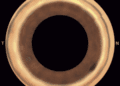

La función giratoria escanea todas las facetas de los 16 espejos en el orden de toma para obtener imágenes de cada porción en varios planos focales, generando imágenes en color de alta resolución en 360º y combinándolas en una sola fotografía. Se puede utilizar como una herramienta complementaria para el diagnóstico oportuno de diversas enfermedades como el glaucoma; las imágenes obtenidas también son una herramienta de enseñanza invaluable para ayudar a los estudiantes a identificar los puntos de referencia anatómicos.

Cada imagen cubre un campo de 4 mm a 38 grados, con una superposición lateral del 20%. El usuario puede seleccionar las imágenes con la mejor calidad en cada faceta, ya que el software genera una reconstrucción lineal de una sola imagen y a 360 grados, que se puede utilizar para el análisis topográfico de los ángulos.

Las imágenes en color de alta resolución de 360º permiten clasificar el ángulo como abierto o cerrado, la evaluación del nivel de inserción del iris, la amplitud del ángulo, el grado de pigmentación trabecular y las áreas de aposición iridotrabecular o sinequias. El Gonioscopio GS-1 es un dispositivo innovador para la evaluación del ángulo iridocorneal, realmente útil para el seguimiento de los pacientes con ángulos estrechos que se sometieron a iridotomía periférica láser. Las características automatizadas de este dispositivo hacen que el procedimiento sea menos dependiente del operador, por lo que es posible que la fotografía sea capturada por un técnico u otro miembro designado del personal.